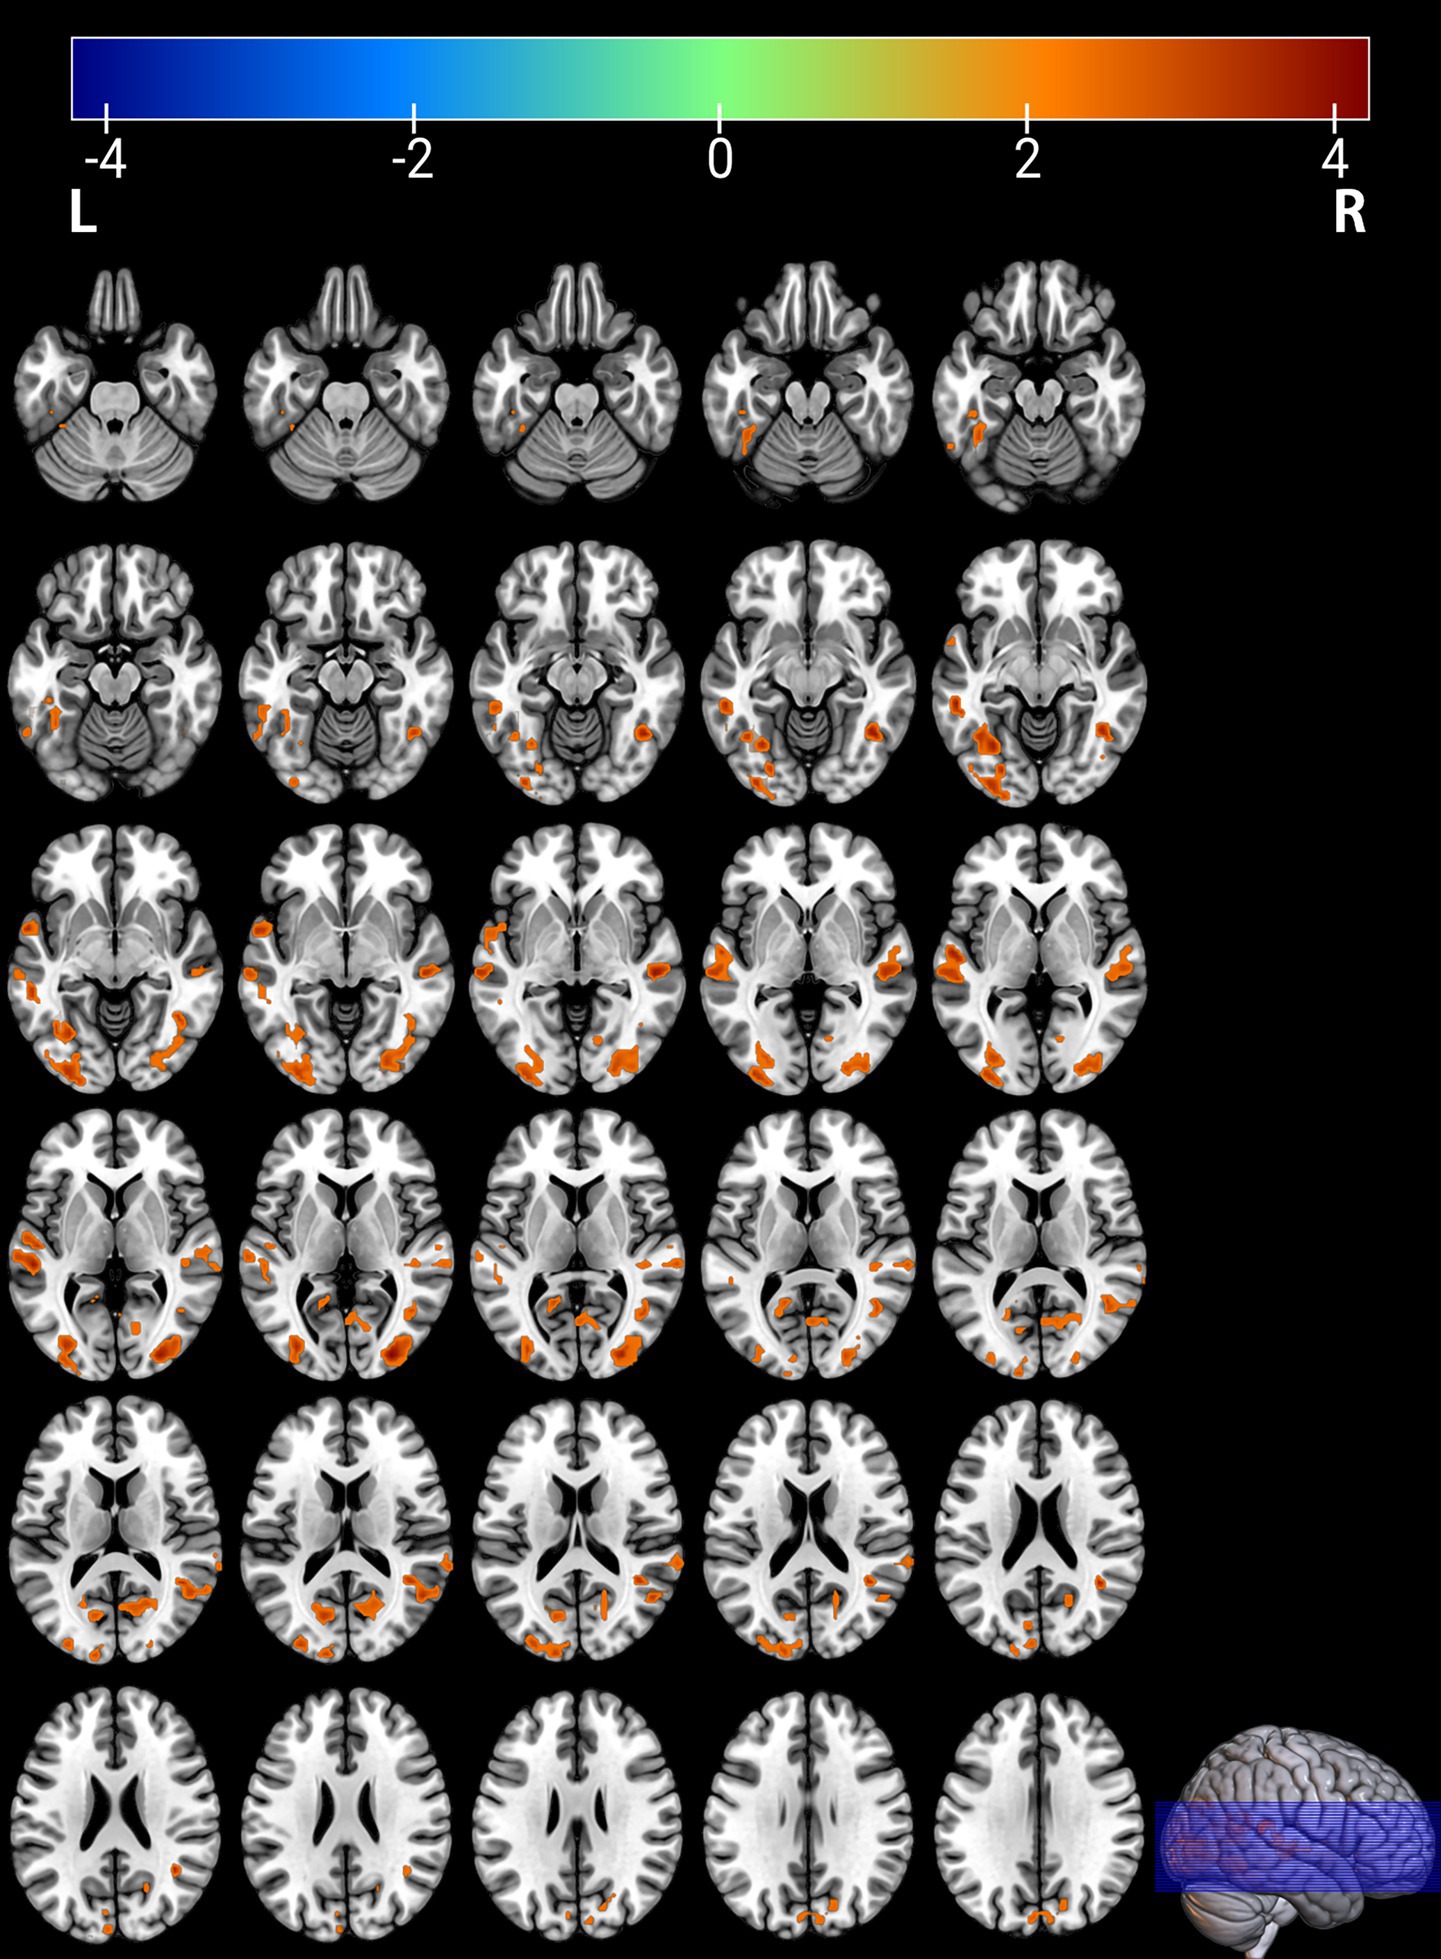

Figure 2

Brain regions with significantly increased ALFF in the PT group compared to the HC group. The results are displayed on 2D axial slices for detailed anatomical localization. Statistical significance was determined by a two-sample t-test, with voxel-wise FDR correction at p < 0.05. The color bar represents the T-value. Warm colors (red) indicate a significant increase in ALFF in the PT group. Significant clusters include the left fusiform gyrus (Fusiform_L), left middle temporal gyrus (Temporal_Mid_L), right middle occipital gyrus (Occipital_Mid_R), right middle temporal gyrus (Temporal_Mid_R), right calcarine cortex (Calcarine_R), right angular gyrus (Angular_R), and left calcarine cortex (Calcarine_L). R, right; L, left.

Comparison between the depressed PT group and the healthy HC group revealed differences in seven brain regions between the two groups (p < 0.05, FDR corrected, Table 2), with Fusiform_L, Temporal_Mid_L, Occipital_Mid_R, Temporal_Mid_R, Calcarine_R, Angular_R, and Calcarine_L increased (Figures 1, 2).

Table 2

| Fusiform_L (aal) | −30 | −66 | −9 | 3.7348 | 338 |

| Temporal_Mid_L (aal) | −54 | −30 | 3 | 4.125 | 176 |

| Occipital_Mid_R (aal) | 30 | −90 | 6 | 4.3296 | 195 |

| Temporal_Mid_R (aal) | 51 | −27 | −3 | 4.0037 | 114 |

| Calcarine_R (aal) | 21 | −66 | 12 | 3.1043 | 93 |

| Angular_R (aal) | 39 | −51 | 24 | 3.8749 | 81 |

| Calcarine_L (aal) | −15 | −72 | 15 | 3.415 | 91 |